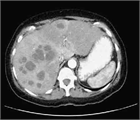

1. 肝膿瘍は、大きく細菌性とアメーバ性の2種類に分けられる。